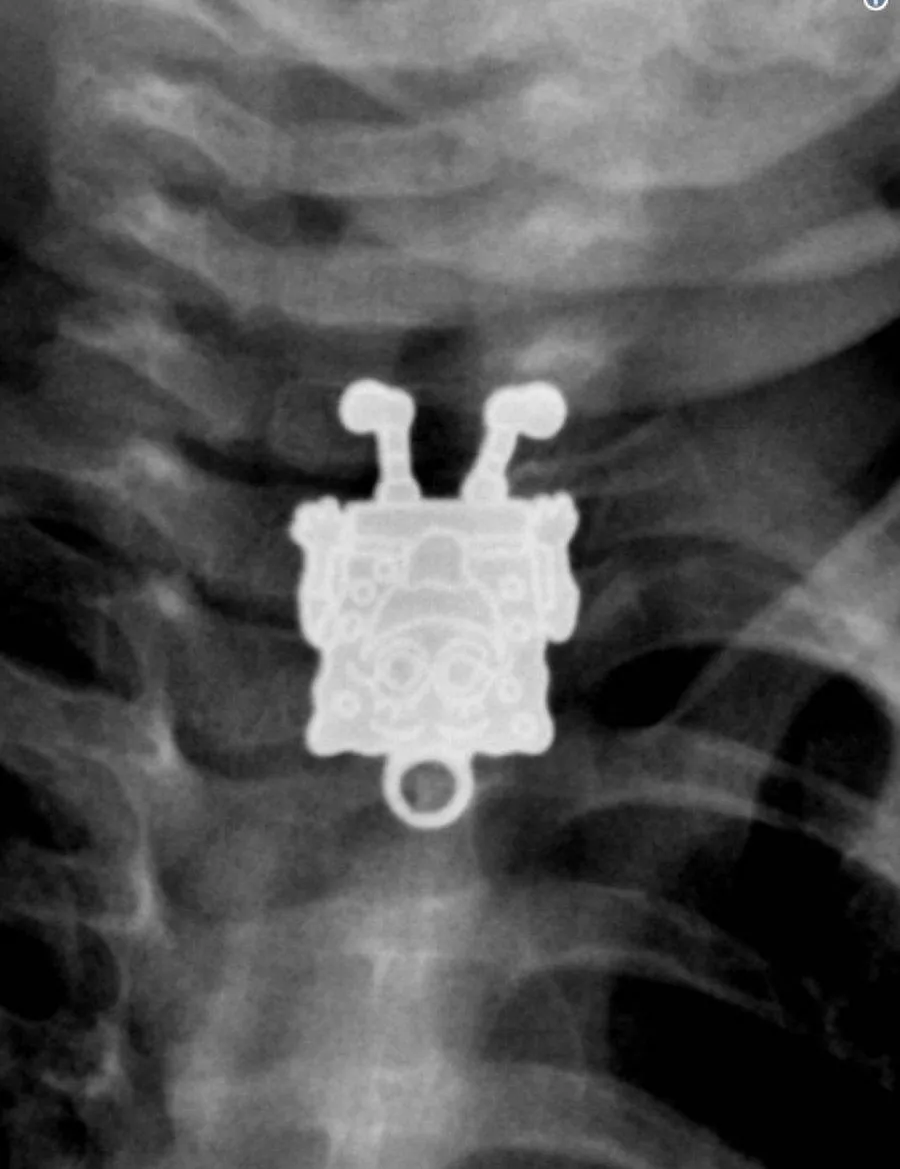

Губка Боб, это ты?!

Фото onedio